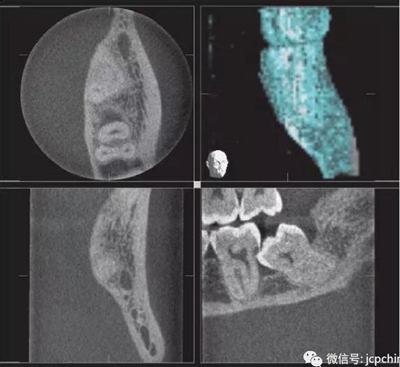

(3)部分容積效應(yīng)產(chǎn)生的偽影

如果探測器中一個(gè)高對比度物體的體積小于體素尺寸,則該對象將會(huì)有效地填充入整個(gè)體素,使其看起來比實(shí)際物體大。牙膠周邊碎片的顯影就是其中一個(gè)很好的例子,如果牙膠周邊碎片的體積小于體素大小,則圖像上會(huì)看起來比實(shí)際的大。